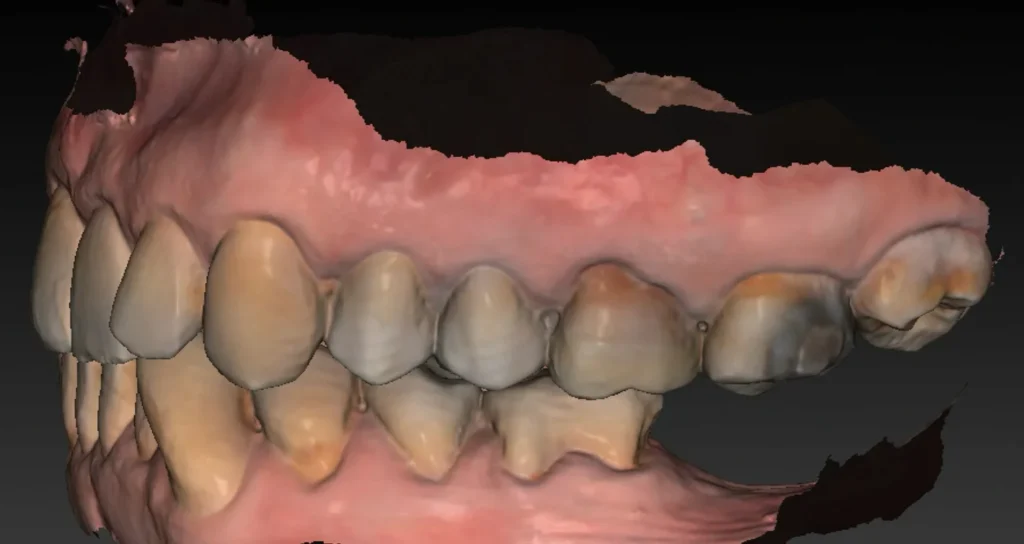

Une empreinte optique est également effectuée. Elle permet :

- de visualiser avec précision le relief gingival et d’identifier les zones nécessitant éventuellement une greffe de gencive ;

- d’évaluer les rapports occlusaux en vue de la future restauration prothétique ;

- d’alimenter la planification numérique en superposant les données optiques au volume osseux issu du Cone Beam.

L’ensemble de ces données permet ensuite de réaliser une planification implantaire précise, fondée sur une analyse tridimensionnelle croisée des tissus durs et mous, et tenant compte des exigences prothétiques.